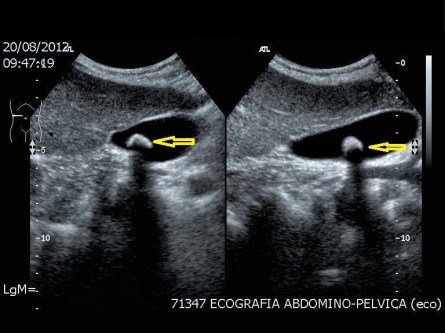

Para estudiar una posible TVP debemos saber conocer donde están la arteria y la vena poplítea…una anterior y otra posterior, una depresible, la vena y otra no, la arteria…mira:

Aquí tienes las dos imágenes, una sin comprimir, donde vemos los dos vasos, cuando comprimimos colapsamos la vena, si la vena no se colapsase sería signo de alarma y valoración inmediata de la Radióloga responsable.

Para conseguir esta imagen colocaremos la pierna afectada apoyando sobre la otra, para flexionarla ligerísimamente y conseguir un mayor retorno venoso, hará que veamos mejor los vasos, sobre todo la vena.